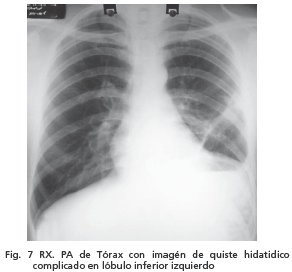

Presentó cuadro clínico de un mes de evolución caracterizado por tos y expectoración mucosa y posteriormente mucopurulenta, por lo que acude a INT, donde se realiza placa de Rx de tórax, en la que se evidencia imagen radiopaca homogénea, de borde circular, bien delimitados en proyección de lóbulo inferior izquierdo (Fig.7).

Fue intervenido quirúrgicamente en septiembre de 2006, hallandosé quiste hidatídico de aproximadamente 20 cm de diámetro que comprometía todo el lóbulo inferior del pulmón izquierdo, además de adherencias de pleura visceral a parietal en algunas regiones de cavidad pleural.